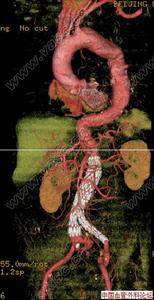

主動脈竇動脈瘤破裂主動脈竇動脈瘤是一種罕見的先天畸形,約占先天性心臟病患病率的2%~3.56%,其破入右室者最多,其次為右房。發生原因主要是胚胎期竇壁中層彈力纖維發育不良,在主動脈內高壓影響下,該薄弱處逐漸變薄擴張,呈囊袋狀突出,當壓力突然增加時破裂,由於主動脈和破入心腔間存在著較大的壓力階差,可產生大量的左向右分流,因而導致全心容量負荷增加,特別是外破口較大或破入右房者,病情進展快,容易發生充血性心力衰竭,部分患者易繼發心內膜炎、心律紊亂、腎功能衰竭等嚴重併發症。臨床多表現為起病急、進展快。一般認為,主動脈竇動脈瘤破裂之前多無明顯症狀和體徵,一旦破裂,即產生劇烈胸痛及顯著的血流動力學改變。破入右室、右房者可出現右心衰竭,呈進行性加重。體徵有胸骨左緣第3、4肋間連續性響亮機器樣雜音,常伴有肺動脈高壓、右心功能不全及脈壓差增大的表現。首次聽診往往有主動脈瓣受損的印象,易誤診為主動脈瓣關閉不全,本例即是此種情況。超聲心動圖是最佳的無創診斷法,可直接顯示主動脈竇動脈瘤的起源形態、突入的心腔位置、竇瘤破口大小、是否合併其他心臟畸形、分流的性質、時相、最大流速,提供血流動力學資料。一旦瘤體破裂,預後不良,可在數周至數月內因嚴重併發症死亡。內科治療只能起到短暫的減輕作用,手術治療往往可以獲得滿意的效果。該戰士因沒有及時手術,導致急性腎功能衰竭並時間過長,多臟器衰竭而死亡。